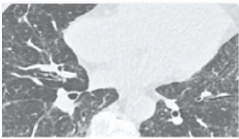

ΑΤΛΑΝΤΑΣ ΑΠΕΙΚΟΝΙΣΗΣ ΑΞΟΝΙΚΗΣ ΤΟΜΟΓΡΑΦΙΑΣ ΘΩΡΑΚΟΣ